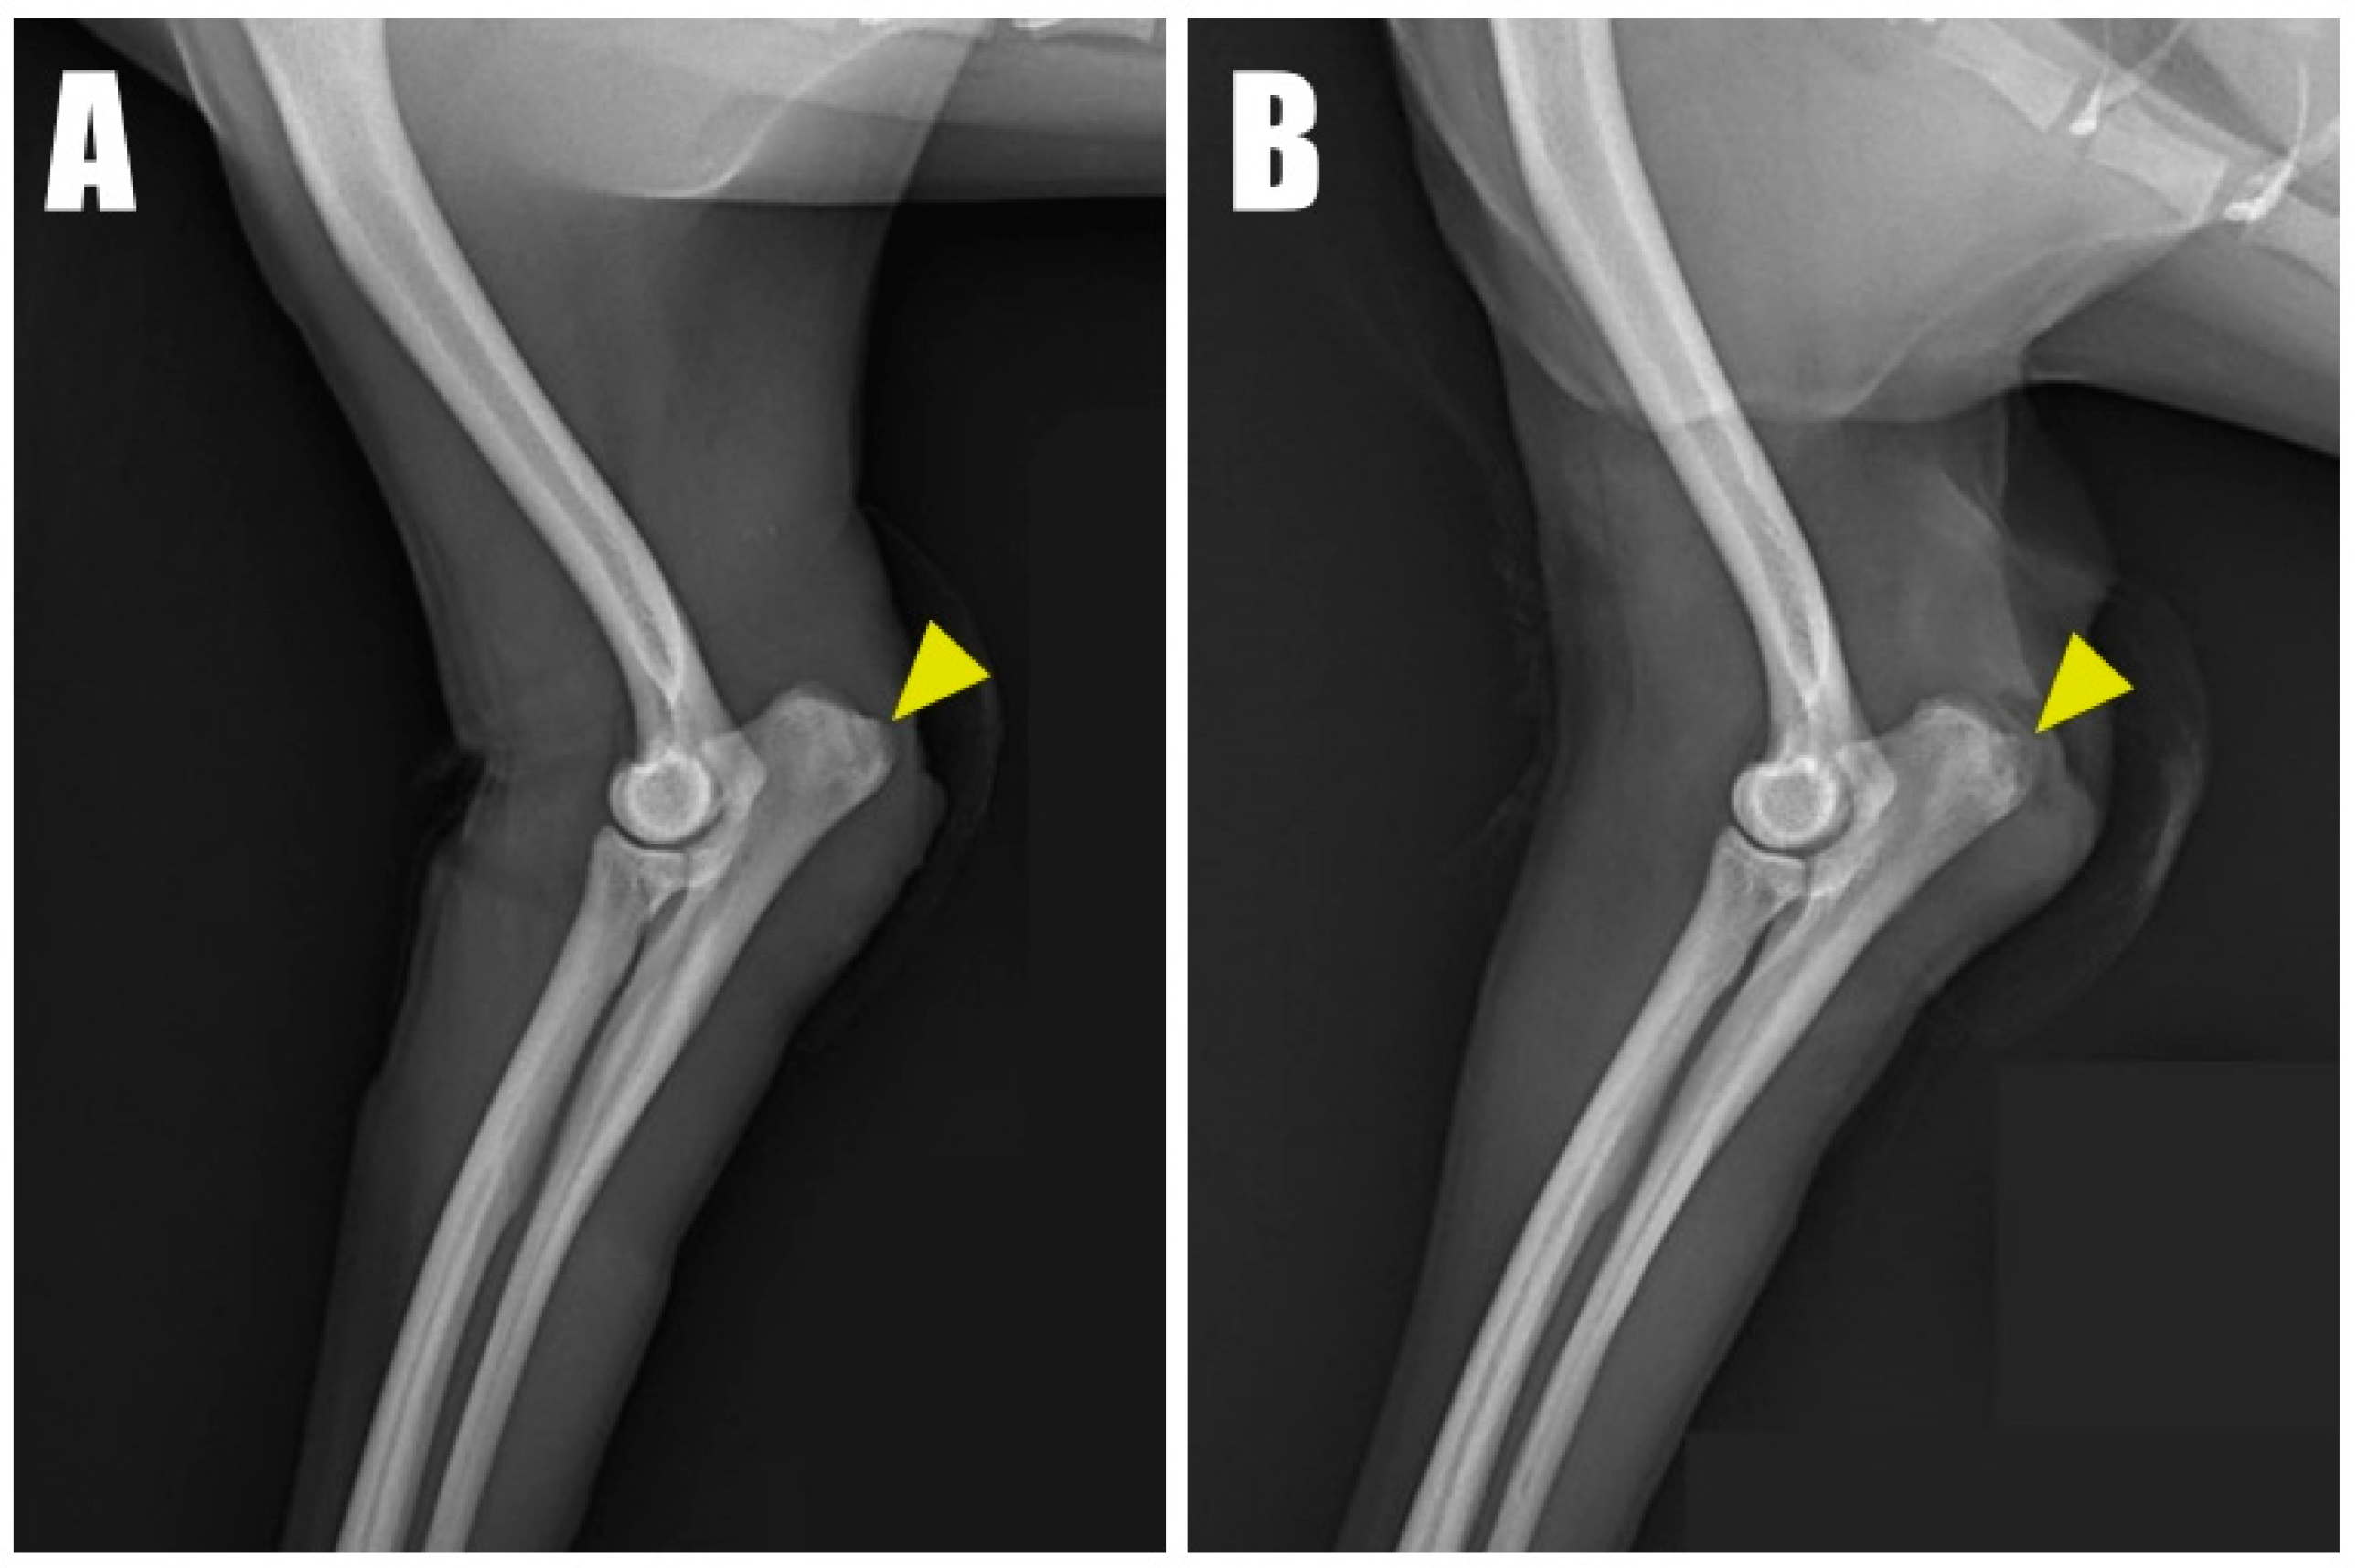

Figure 2. Radiolucent opacity (yellow arrowhead) was visible on the olecranon in radiographic images of the (A) right and (B) left forelimbs.

A 2-year-old, 4.5 kg, intact female Pomeranian was referred to a veterinary medicine teaching hospital with bilateral open wounds (Video S1, Figure 1A) at the olecranon region. The dog presented with a history of bilateral forelimb lameness and crouch gait (Figure 1B) as follows: four weeks in the left forelimb and three weeks in the right forelimb, each following a fall from a height. Physical examination revealed a pain response and nodular formation in the proximal region of the olecranon, with no extension response during the triceps brachii squeeze test. Radiographs revealed radiolucent opacities on both sides of the olecranon (Figure 2A,B), and ultrasonography identified defects (Figure 3A,B) at the triceps brachii tendon and olecranon junction, accompanied by inflammation and edema. Notably, the distal end of the proximal tendon appeared hyperechoic compared with the normal tendon. Based on the diagnosis of bilateral triceps brachii tendon disruption, believed to be of traumatic origin, and with the exact cause remaining open to interpretation, surgical repair was indicated. The initial management of the open wounds involved sugar dressing and debridement. Pre-anesthetic evaluation through blood samples, assessing electrolytes, and complete blood count (CBC), revealed all values within normal limits.

Postoperative radiographs and ultrasound images (Figure 6) were taken to confirm the position and connectivity (Figure 7) of the tendon on the olecranon. On the right side (Figure 6A), the transverse hole was observed to be close to the caudal cortex, while the remaining bone tunnels were confirmed to have been drilled as intended. For analgesia, remifentanil was continued for three days postoperatively at 0.1~0.3 ug/kg/min with constant rate infusion. The other postoperative therapy including antibiotics (amoxicillin and clavulanic acid, 12.5 mg/kg BID, for 14 days/Clindamycin, 11 mg/kg BID, for 14 days), NSAID (meloxicam, 0.1 mg/kg SID for 14 days), and gastrointestinal protectant (esomeprazole, 1 mg/kg SID for 14 days) were administered.

Figure 6. Immediate postoperative radiograph of the (A) right forelimb showing the transverse hole (arrowhead) in the caudal aspect of the ulna. (B) A corresponding image of the of the left forelimb. Six-month postoperative radiograph of the (C) right and (D) left forelimb.